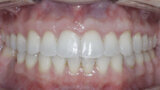

New Age orthodontics and orthopaedics with temporary anchorage devices